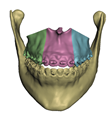

2.5.1. Bones

- In maxillary procedures, the maxilla is separated from the skull through a Lefort osteotomy, classified based on its anatomical level. In this cohort, the distribution of cases is: 8 Lefort I cases and 1 Lefort II case; one patient did not undergo maxillary surgery. Moreover, after a Lefort I osteotomy, the maxilla may be segmented (typically into three fragments) in order to expand the upper arch. Maxilla segmentation was applied to 6 patients in this cohort.

- In mandibular procedures, the mandible may be sagittally split on both rami (bilateral sagittal split osteotomy, BSSO) or only one ramus (unilateral sagittal split osteotomy, USSO). In this cohort, the distribution of cases is: 7 BSSO cases, 1 USSO case; two patients did not undergo mandibular surgery. Additionally, a chin osteotomy or genioplasty may be also performed. Genioplasty was applied to 1 patient in this cohort.